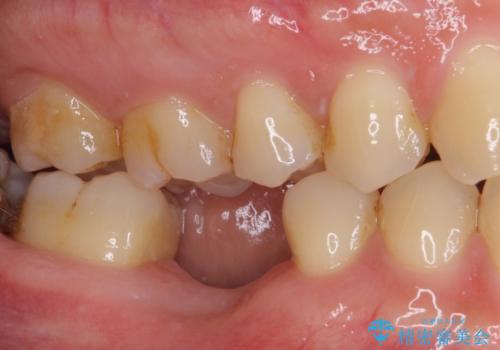

- 大学病院でインプラント治療を進めていたものの、予約のタイミングが合わないとのことで来院された患者様です。

欠損部位の骨や歯肉の状態は非常に良く、速やかにインプラント埋入を行い、補綴治療を進めて行くことのできる状態でした。